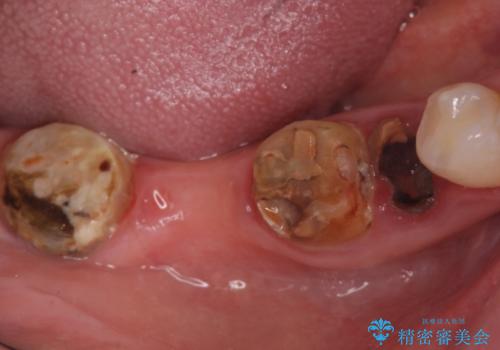

- 右下の奥歯の被せ物が外れてしまったので診て欲しいといらっしゃった方の症例です。

右下7は欠損しており、右下5は保存不可能だったため、インプラントによる欠損補綴を行いました。